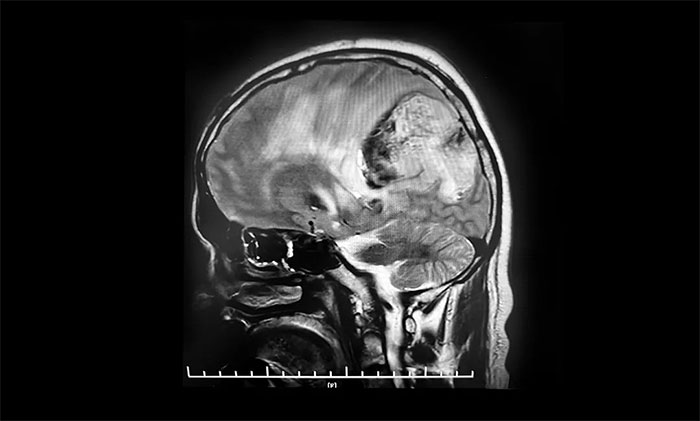

患者為45歲中年男性,在2009年4月體檢時發(fā)現(xiàn)顱內(nèi)占位性病變,就診上海某三甲醫(yī)院行頭顱MRI增強提示,顱內(nèi)有一8x8cm占位性病變,考慮腫瘤巨大并且位置深在,給予化學(xué)藥物治療。2021年,求醫(yī)鄭州某醫(yī)院,給予中藥治療。2022年在當(dāng)?shù)厝揍t(yī)院復(fù)查頭顱MRI提示占位性病變,繼續(xù)給予化學(xué)藥物治療。

今年10月7日,患者突發(fā)意識不清,伴右手不自主抖動,呼喚有反應(yīng),反應(yīng)遲鈍,立即就診于當(dāng)?shù)蒯t(yī)院。行頭顱增強MR提示:左側(cè)額頂葉、胼胝體體部及壓部、丘腦占位伴左側(cè)頂葉占位,范圍較前明顯增大,均以彌漫性膠質(zhì)瘤考慮伴左頂葉腫瘤卒中出血。10月11日,患者癥狀較前加重,出現(xiàn)嗜睡,反應(yīng)遲鈍,右側(cè)肢體肌力明顯下降。當(dāng)?shù)蒯t(yī)院表示無法救治,希望渺茫。

之后,患者家屬抱著最后一線希望,慕名求醫(yī)上海藍(lán)十字腦科醫(yī)院。神經(jīng)外科特需專家李士其教授、周范民教授、黎軍主任,神經(jīng)外科6B病區(qū)潘仁龍主任對患者影像資料、病史進行了會診。李士其教授指出,根據(jù)影像資料結(jié)合病史,患者主要是吃了過多化療藥物導(dǎo)致腫瘤組織結(jié)構(gòu)改變,發(fā)生腫瘤卒中,導(dǎo)致出血,產(chǎn)生顱內(nèi)高壓導(dǎo)致患者昏迷,仍然有手術(shù)希望的,但是風(fēng)險也是不言而喻。

頭顱MRI平掃+增強+DWI+MRA提示,左側(cè)頂枕葉巨大腫瘤伴局部瘤卒中,幕上腦室系統(tǒng)、腦干受壓變形,中線結(jié)構(gòu)右移19mm,大腦鐮下疝形成。李士其教授等專家團隊會診指出,患者腦內(nèi)巨大占位,性質(zhì)不明,并且患者已經(jīng)發(fā)生腦疝昏迷,生命危在旦夕,應(yīng)盡快進行手術(shù)治療,挽救患者生命,同時明確病理診斷。